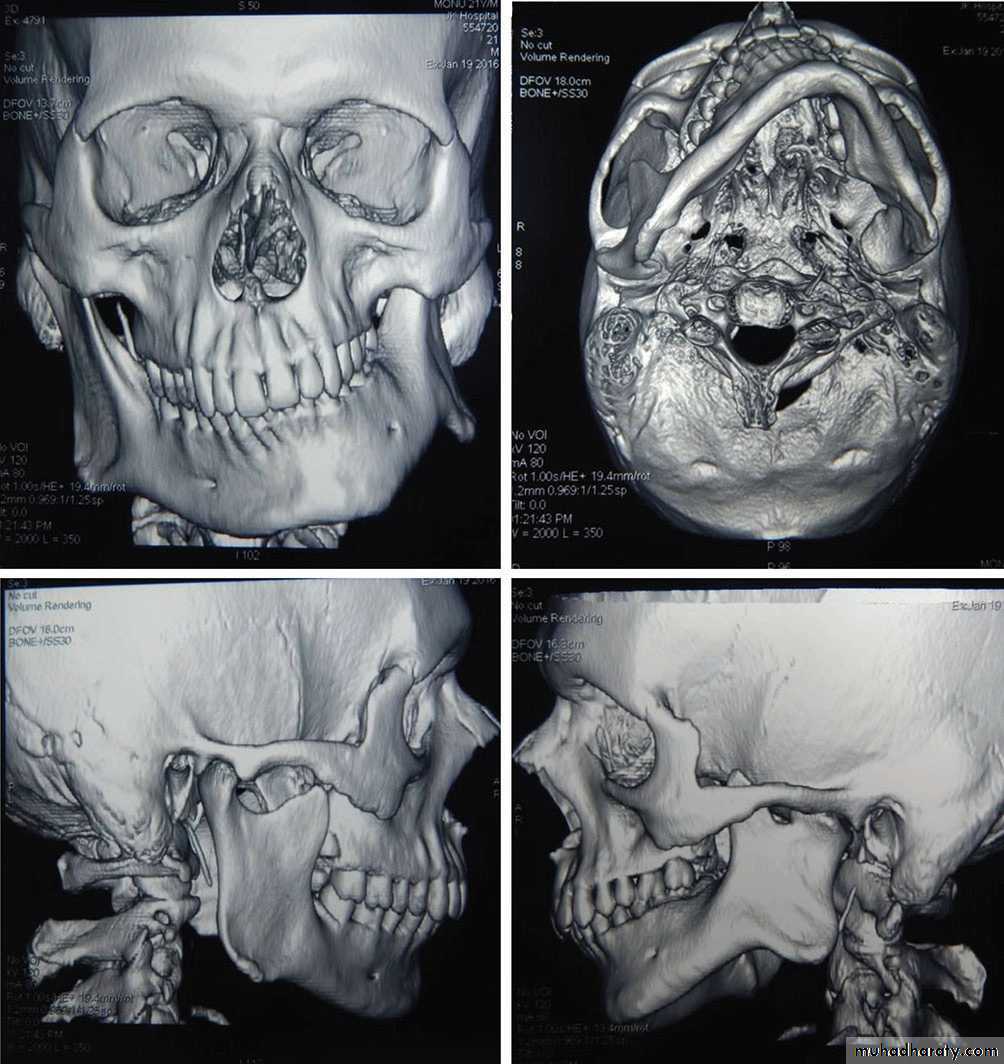

• Malignant Tumors:(black arrows)

May be asymptomatic or patients may have symptoms of TMJ dysfunction (pain, limited mandibular opening, mandibular deviation and swelling)* Radiographic Features:

Variant degree of bone destruction with ill defined, irregular margins

CT modality of choice

MRI useful for displaying extent of involvement into surrounding tissues.

* Treatment:

Surgical removal of tumor.

May include radiotherapy and chemotherapy.